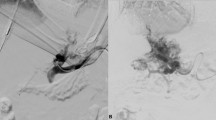

In cases where the percutaneous transhepatic or percutaneous transsplenic approach proved ineffective, a midline vertical incision was performed below the umbilicus on the abdomen. This was done to expose the tributaries of the SMV with the assistance of surgeons. A 6F catheter sheath was then inserted into the main trunk of the SMV, and a 14 G metal tube and a 5.2F blue catheter, components of the RUPS-100 puncture system, was guided along the wire to the PV trunk or proximal SMV (point B). Under fluoroscopy, a pre-placed balloon in the posterior segment of the IVC was punctured, establishing a working channel in the reverse direction. The stent was subsequently implanted and dilated using the same method to achieve effective portosystemic shunting (Fig. 2).

A 74-year-old male patient, who has been dealing with liver cirrhosis for 30 years, has been suffering from recurrent episodes of esophagogastric variceal hemorrhage and recurrent ascites for the recent three years. Previous interventions, including ESVD and LVP, have proven to be ineffective. a–b The multiplanar reconstruction from the spiral-enhanced CT scans demonstrated cavernous transformation of the portal vein, with patent mesenteric veins. c The transabdominal mesenteric venography reveals a patent mesenteric venous system and the presence of extrahepatic collateral vessels. d Utilizing a 14 G metal tube, part of the RUPS-100 apparatus, the tube was directed to the proximal region of the SMV with the aid of a guidewire. Following this, a pre-inserted balloon located in the posterior segment of IVC was successfully punctured. e A stent was successfully placed between SMV and IVC. f The spiral-enhanced CT with multiplanar reconstruction images show that the stent is patent at 1 month after TEPS. PV portal vein, IVC inferior vena cava, SMV Superior mesenteric vein, ESVD Endoscopic selective varices devascularization, LVP large-volume paracentesis